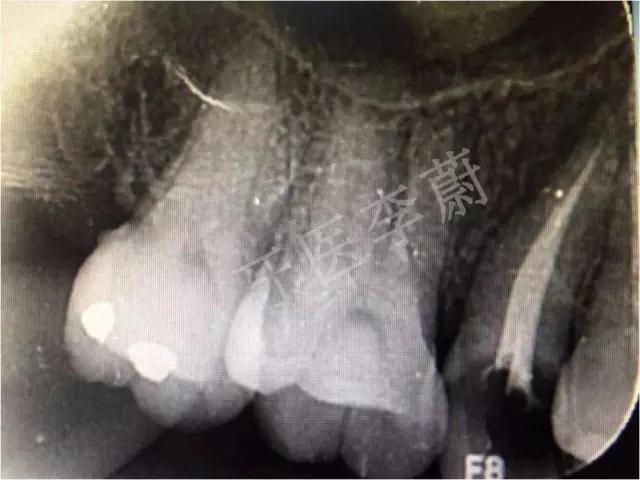

X片示:15残冠影,根尖有骨密度降低影。

局部X牙片